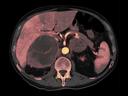

More and more radiologists are relying on the rich diagnostic possibilities offered by True Dual Energy imaging on Siemens Healthineers' CT scanner fleet ranging from SOMATOM® Scope Power up to the outstanding SOMATOM Force.

The question is: What makes True Dual Energy stand out? Look for these three criteria: crisp images with the option for even sharper contrast and significant artifact reduction; no extra dose in either Single Source or Dual Source Dual Energy scans, and a broad applicability for virtually all clinical questions and patients.

Discover Dual Energy (DE) spectral imaging. It’s the difference between images and answers. Visualization and characterization. Qualification and quantification. Built into all of our CT scanners, it delivers powerful performance, incredible versatility for your entire patient population, and exceptional ease-of-use – all while integrating seamlessly with your current workflow.